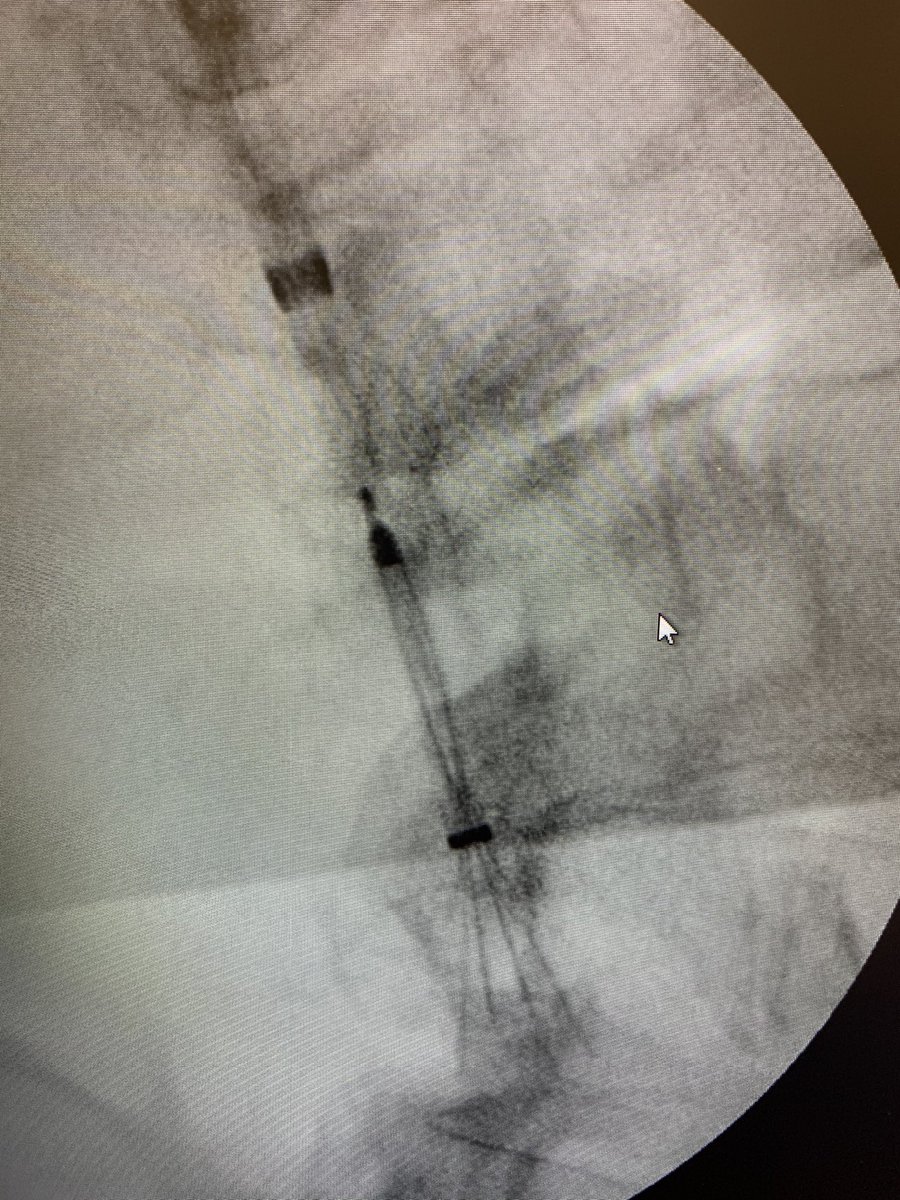

This patient presented with severe leg edema, iliocaval thrombus with 12 year old #IVCfilter. After a night of lysis a large vol of chronic appearing clot persisted. Was able to get most of it out with a few passes with the Inari T20 from popliteal access. #iRad

#filterout with a #clotout bonus procedure for a le olde HookClot. 16 French suction thrombectomy for the win. Only a tiny residual filling defect on the completion cavogram. Will continue on NOAC for another month. #iRad #IVCFilter